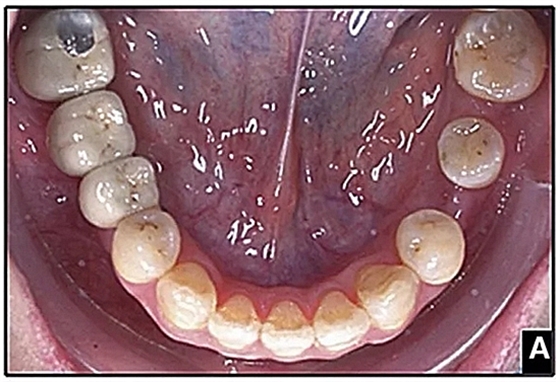

36歲;女性;尋求下頜左后方區(qū)域間隙管理的建議(圖1和圖2),通過(guò)治療獲得了良好的牙頜面效果(圖3和圖4)。她被診斷患有骨性I類和代償性牙性II類錯(cuò)合畸形,并且上頜左側(cè)尖牙缺失(圖1和2)。大約七年前,由于不可修復(fù)的齲齒,拔除了下頜左側(cè)第一和第二磨牙(圖5)。37相鄰的第三磨牙向近中移動(dòng)并傾斜入間隙,導(dǎo)致無(wú)牙頜間隙減小至約14 mm(圖2和圖5)。臨床和影像學(xué)評(píng)估顯示多發(fā)性齲損和在下頜右側(cè)567處有一不良的固定橋修復(fù)體(圖1和5)。此外,下頜左中切牙缺失,造成下頜中線向左側(cè)偏移約3 mm(圖1和圖2)?;颊咦栽V,她的右上第一前磨牙和左上尖牙在13歲時(shí)由其家庭牙醫(yī)拔除,因?yàn)樗鼈儽蛔枞筋a側(cè)萌出(圖1)。上頜第二磨牙缺失(未知病因),并且相鄰的第三磨牙已經(jīng)轉(zhuǎn)移到第二磨牙間隙中。如補(bǔ)充材料所示,美國(guó)正畸學(xué)差異指數(shù)DI是28分。種植體部位(下頜左側(cè)和右側(cè)第一磨牙)由于復(fù)雜性得到額外4分(補(bǔ)充材料)。

圖1. 治療前面部和口內(nèi)照片